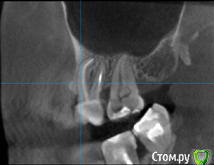

татьяна tat Опубликовано 4 сентября, 2016 Автор Поделиться Опубликовано 4 сентября, 2016 (изменено) скажите пожалуйста...по кт тоже видно ,что каналы не пролечены? Изменено 4 сентября, 2016 пользователем татьяна tat Ссылка на комментарий

Beznika Опубликовано 8 сентября, 2016 Поделиться Опубликовано 8 сентября, 2016 на 5 ке материал вывели за апекс. резекцию возможно придётся делать верхушки корня... + карман у вас есть за 6кой. а так всё равно перелечивать надо... масса пористая в каналах и не гомогенная. (не однородная) Ссылка на комментарий

татьяна tat Опубликовано 8 сентября, 2016 Автор Поделиться Опубликовано 8 сентября, 2016 (изменено) на 5 ке материал вывели за апекс. резекцию возможно придётся делать верхушки корня... + карман у вас есть за 6кой. а так всё равно перелечивать надо... масса пористая в каналах и не гомогенная. (не однородная) в каком случае мне грозит резекция? и что с карманом делать?может на срезах так видно...но врач оч. хорошей клиники,на очном приеме,смотря на компьютере кт,сказала,что каналы пролечены на 5+.....не считая того,что немного выведено материала Изменено 8 сентября, 2016 пользователем татьяна tat Ссылка на комментарий